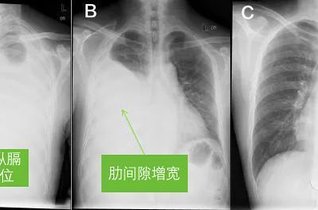

图文教程 手把手教你看胸片! 丁香园